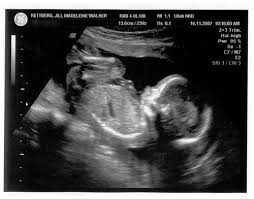

Os efeitos ocultos do ultrassom

O ultrassom foi desenvolvido no início dos anos oitenta, e seu uso em obstetrícia foi rapidamente se estendendo e substituindo o raio-X que, havia-se descoberto recentemente, afetava negativamente o feto em formação.

No início dos anos noventa, o ultrassom já se havia tornado uma ferramenta rotineira nos exames pré-natais, cujos aspectos positivos, como a possibilidade inédita de fazer diagnósticos pré-natais e do casal ver o filho se mexendo na barriga, ao vivo, eram amplamente difundidos, enquanto seus efeitos colaterais permaneciam ainda pouco conhecidos, pouco estudados e, sobretudo, pouco divulgados.

Até hoje, poucos sabem que o ultrassom não é apenas uma câmera que vê o bebê live no útero, e sim uma onda de ultrassons que é lançada na direção do feto e reverbera nos seus tecidos, criando um “eco”, que é captado pela máquina, que monta então uma imagem na tela do computador.

Acontece que essa onda de ultrassom é capaz de modificar os tecidos nos quais reverbera, aumentando sua temperatura. O uso prolongado do ultrassom pode causar um aumento de até 1°C nos tecidos cerebrais do feto, o que pode causar problemas. Tem-se observado um maior número de bebês com lateralidade invertida (canhotos) nascidos desde o início do uso do ultrassom como rotina pré-natal.

E o aquecimento produzido pelo ultrassom não afeta apenas os tecidos humanos, mas também os gazes que se encontram dentro dos tecidos, fazendo-os se expandir e estourar os tecidos, o que é chamado de cavitação. O uso prolongado do ultrassom pode produzir danos cerebrais por cavitação do tecido cerebral, que são permanentes.

O Ministério da Saúde e a Organização Mundial da Saúde recomendam que sejam feitos poucos ultrassons durante a gestação (não seriam necessários mais do que 3), e que sejam sempre com recomendação médica, e não para o simples prazer dos pais de “ver seu filho na telinha”.

Outro problema gerado pelo uso do ultrassom é o aumento do stress pré-natal, graças a diagnósticos pouco confiáveis. Muitas vezes usado para determinar a idade gestacional do feto, o ultrassom tem um margem de erro de duas semanas para mais ou para menos, o que significa que um bebê com idade gestacional de 38 semanas no ultrassom (considerado a termo) pode ter na verdade 40 semanas (plenamente a termo) ou então 36 semanas (prematuro).

O ultrassom, na realidade, não é uma ferramenta apropriada de diagnóstico: todos os diagnósticos feitos graças ao ultrassom devem ser verificados com exames apropriados. O ultrassom é origem de muitos resultados equivocados, os chamados “falsos-positivos” e “falsos-negativos”, que são geradores de angústia no casal. O stress materno afeta o desenvolvimento do bebê, portanto, o ultrassom que causa stress na mãe afeta negativamente o desenvolvimento fetal.

Em alguns países da Europa, onde o aborto é legalizado, relatam-se muitos casos de mulheres que optam pelo aborto por causa de diagnósticos feitos com o ultrassom e acabam abortando fetos perfeitamente saudáveis. Estudos recentes apontaram que não existe nenhum benefício comprovado no uso do ultrassom de maneira rotineira durante o pré-natal.